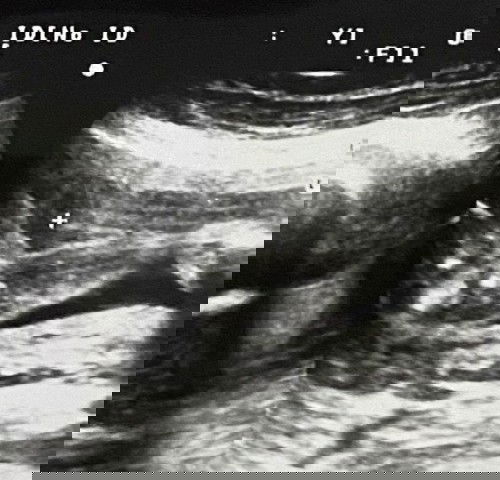

ตั้งแต่ครรภ์30วีค หมอนัดซาวทุก2อาทิตย์ นน.ลูกน้อยทุกครั้งเลย จนตอนนี้34วีคแล้ว นน.ลูก1912เองค่ะ โดนหมอบ่นเลย (ท้อง8เดือนครึ่งนน.แม่ขึ้นมาแค่9โล) หมอบอกให้แม่ทานเยอะๆหน่อย คือเราทานเยอะแล้ว แบ่งคาบทานระหว่างวันเพิ่มด้วย ในแต่ละวันเราพยายามทานโปรตีนให้มากที่สุด เมนูในแต่ละวันก็ข้าวไรซ์ พวกเนื้อ นม ไข่ กล้วย ปลา บางวันก็ผัดผัก บางวันมีทานตับเสริมอาทิตย์ละ3-4วัน มีทานขนมขบเคี้ยวบ้าง ของหวานบ้าง พวกเค้กเบเกอรี่ก็ทาน มื้อเสริมจากปกติทานวันละ3-4มือ ตอนนี้ทานแทบตลอดเวลาเลยค่ะ แทบไม่ปล่อยให้ท้องว่าง จากเมื่อก่อนจะจะกินนมวันละมื้อ คือชงแอนมัมผสมจมูกข้าวทานแค่ช่วงเช้า ทานไข่ต้มวันละฟอง ตอนนี้เราเพิ่มไปอีก คือชงนมแอนมัมตอนเช้า ระหว่างวันเสริมแอนมัมกล่องหรือนมถั่วเหลืองอื่นๆ ก่อนนอนชงนมแพะเสริมไปอีก ไข่ต้มก็ทานวันละ2-4ฟอง มื้อว่างก็กินโยเกิร์ต กินผลไม้ คือเรากินเยอะมากๆ แต่ล่าสุดนน.ลูกก็น้อยอยู่ดี **เราเป็นเลือดจางด้วยค่ะ หมอบอกให้ทานเยอะอีก ไม่อยากจะเครียด แต่คือทำทุกอย่างแล้ว #ขอคำแนะนำหน่อยค่ะ #ใครมีประสบการณ์ #ขอบคุณสำหรับคำตอบค่ะ